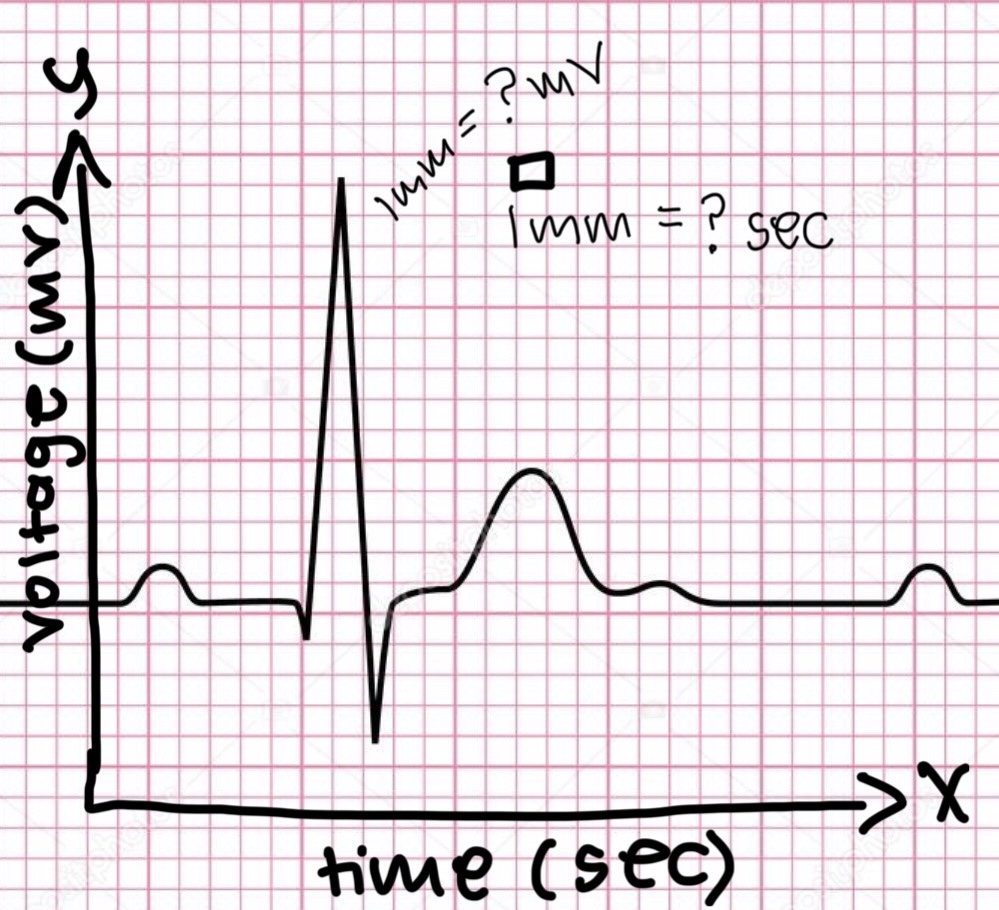

P wave

atrial depolarization

Precedes atrial contraction

QRS complex

ventricular depolarization

Precedes ventricular contraction

T wave

ventricular repolarization

PR interval

Name #1

QRS interval

Name #2

QT interval

Name #3

TP interval

Name #4

PR interval

time from beginning of the P wave to the beginning of the QRS complex

QRS interval

Time from beginning of the QRS complex to the end of the QRS complex

QT interval

Time from beginning of QRS complex to the end of the T wave

TP interval

Time from end of T wave to the beginning of P wave

RR interval

Distance from the peak of one R wave to the peak of the next

0.04

The x axis is time in seconds.

1 mm equals……. seconds?

0.1

The y axis is voltage in mV.

1mm equals ….. mV?

HR = 1500/x mm

Equation for HR or bpm

20

If the ventricular rate is 75 contraction/minute, what is the RR interval in millimeters (mm)?